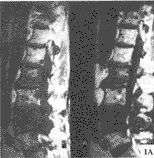

2.2 脊柱转移癌的MRI特点 骨髓被转移癌浸润导致T1驰豫时间延长及相应T1像信号强度的降低,转移癌表现为局灶性或弥漫性低信号,区别于T1加权像高信号的正常骨髓背景(图1A)。大多数转移癌T2加权像呈高信号(图1B)。钆-DTPA缩短T1弛豫时间,在T1加权像增强扫描,使骨病损信号增强,可以帮助鉴别那些诊断困难的脊柱转移癌。

图1 MRI

T1像(A)T10、L2及L4椎体弥漫性低信号,且L1,3,5椎体局灶性低信号;T2像(B)T10、L2及L4弥漫性高信号,部分椎体相当于T1像的部位局灶性高信号